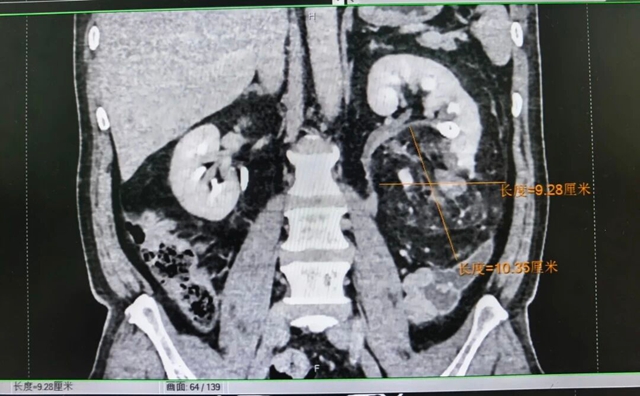

“立即联系CT室,寻找出血根源”。影像学报告显示,王先生的双肾不仅有了肾结石,左肾中下极还藏着一个“巨型炸弹”——一个直径约 9×10cm 的肿块,大小堪比一个拳头,初步考虑为肾错构瘤。更危险的是,这个肿瘤已经破裂,正是它的出血导致了王先生的肉眼血尿。

术前检查影像